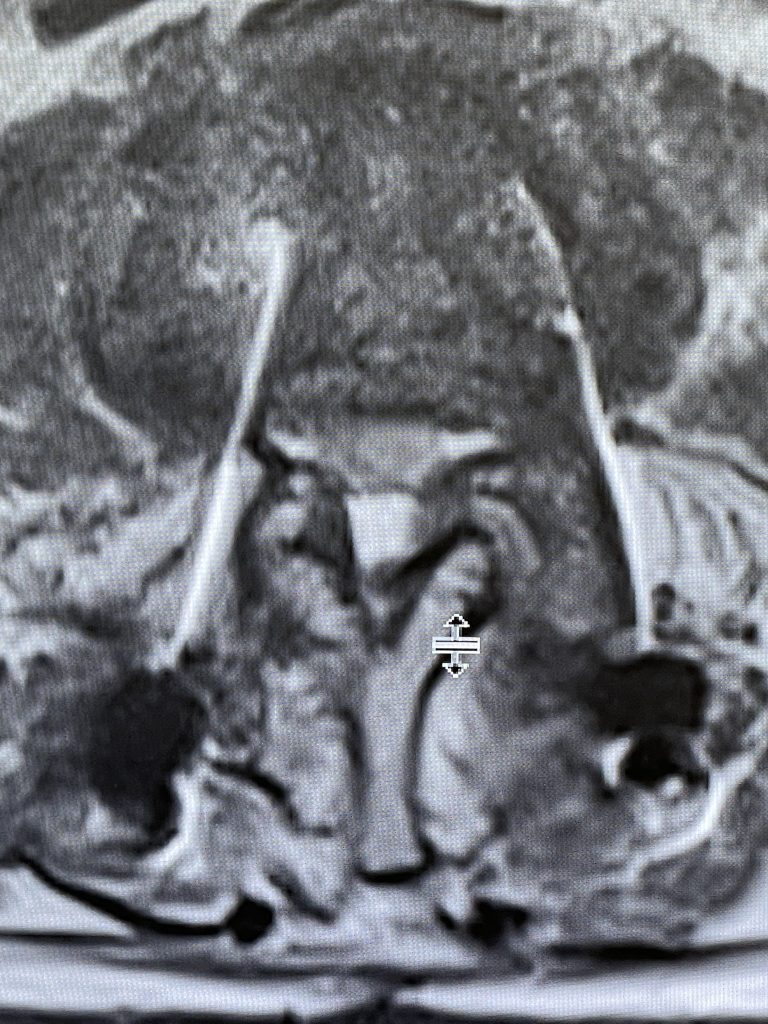

Figure 2. Axial T2 MRI of the lumbar spine demonstrating L2-3 stenosis due to significant facet arthropathy.